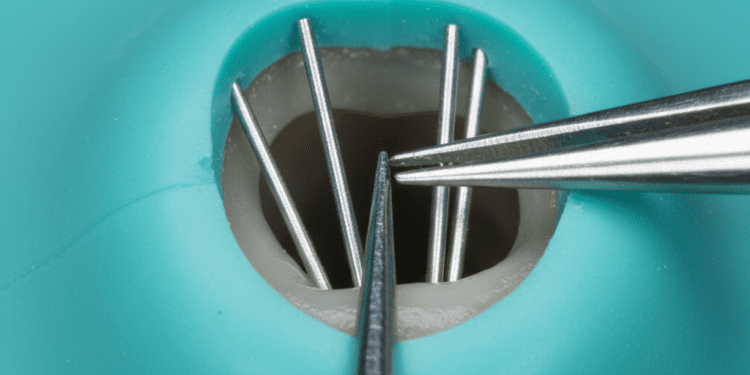

Para casos iniciais, o controle dos fatores de risco e a aplicação tópica de flúor, sob a forma de vernizes ou uso diário de cremes dentais fluorados, são eficazes para remineralizar as áreas comprometidas.

Nos casos mais avançados, a odontologia restauradora oferece opções como resinas compostas, facetas, coroas e outras restaurações que protegem o dente, recuperando forma e função. A escolha do material e técnica depende da extensão da erosão, da localização dos dentes afetados, da estética e da função mastigatória.